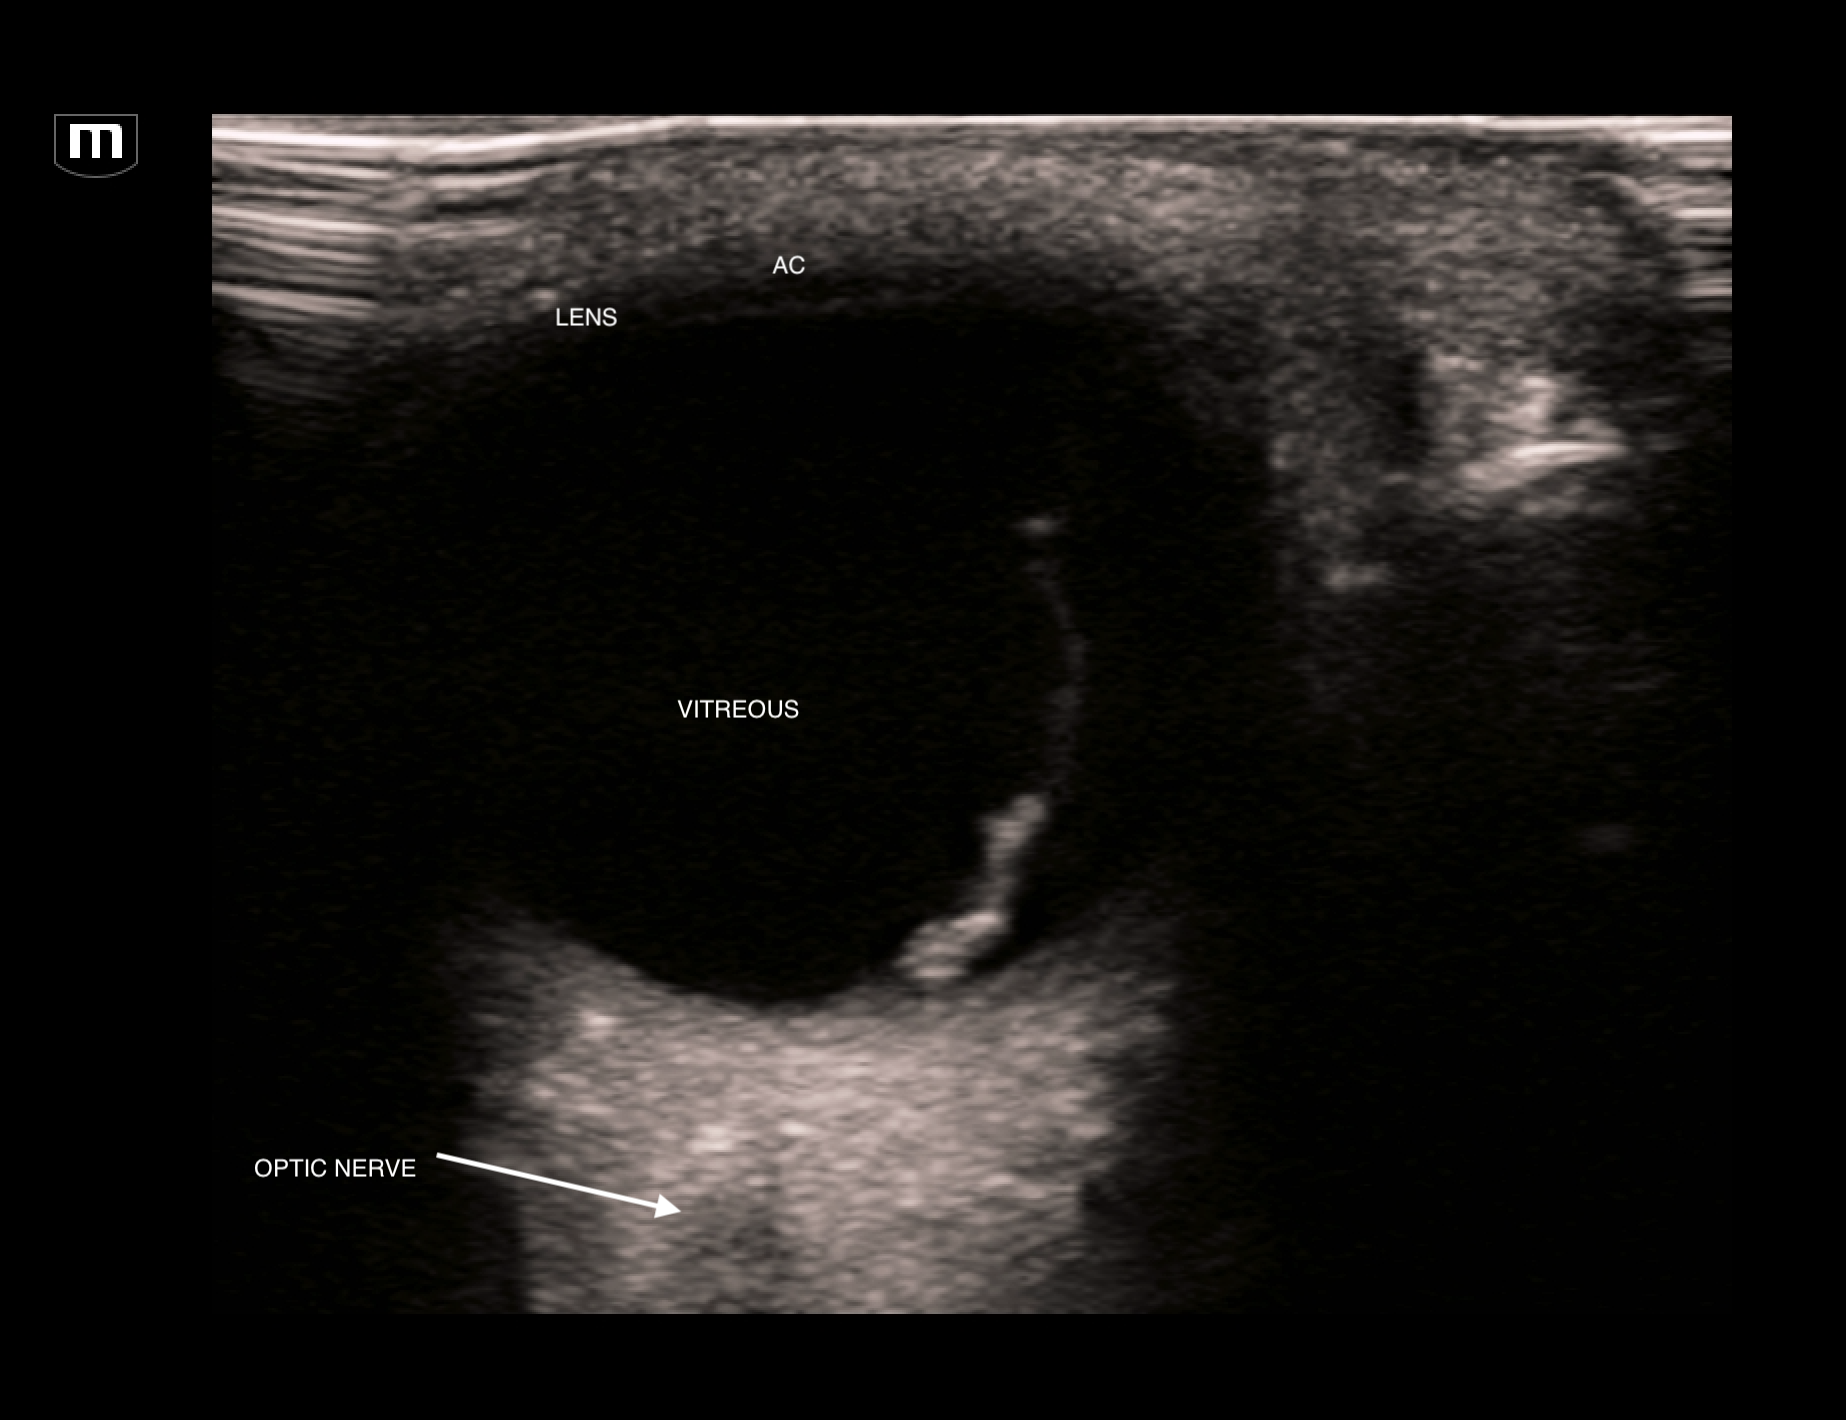

The EDUS showed this:

L orbit trans (annotated below)

This scan shows a thick hyperechoic membrane within the anechoic vitreous seeming to originate from the optic disc. This is typical of retinal detachment. Always fan through the orbit to try and image the optic nerve coming in to the orbit. A retnal detachment will be seen to be tethered to the optic disc. It does not cross over to the other side.

Clip below of imaging to define the optic nerve and the fact that the membrane does not cross the optic disc.

Clip of retinal detachment showing optic nerve and membrane tethered to the optic disc